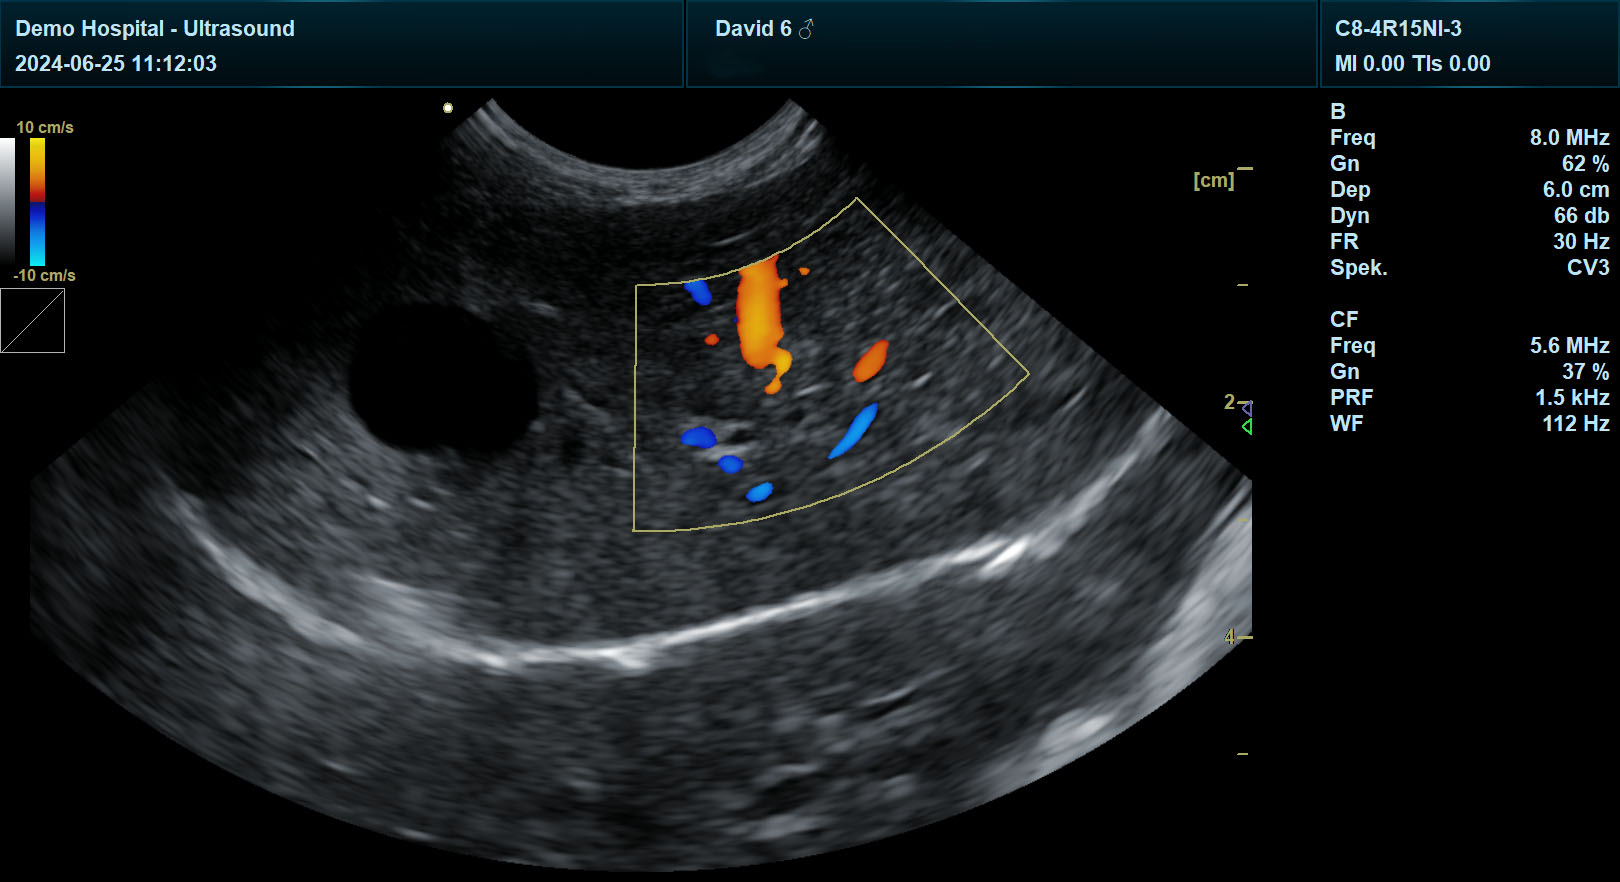

血管评估:门静脉分支表现为外周有壁、中央无回声的管状结构,正常管径<0.5cm;肝静脉壁通常不可见,若出现高回声壁,提示静脉血栓形成。宜慧康彩超的彩色多普勒模式可实时显示门静脉血流方向与速度,辅助判断血管狭窄或栓塞。

三、临床案例:宜慧康彩超在肝肿瘤诊断中的应用

一只8岁雄性金毛犬,因食欲减退、腹围增大就诊。常规超声检查发现肝右叶存在3.2cm×2.8cm混合回声团块,边界不清,内部回声不均。使用宜慧康彩超进行进一步评估:

弹性成像:团块硬度值显著高于周围肝组织(85kPa vs. 25kPa),提示恶性肿瘤可能。

彩色多普勒:团块内部检测到丰富血流信号,阻力指数0.65.符合肝细胞癌血流特征。

3D重建:显示肿瘤侵犯肝右静脉,指导手术方案制定。

术后病理确诊为肝细胞癌,与超声诊断完全一致。该案例体现了宜慧康彩超在肝肿瘤早期诊断、鉴别诊断及治疗决策中的关键作用。